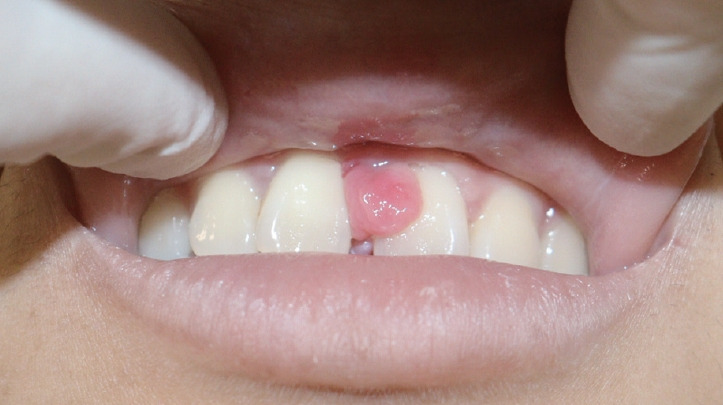

This case report describes a rare occurrence of pyogenic granuloma (PG) in the hard palate deviating from its typical gingival location that led to the formation of an alveolar cleft. The aggressive growth pattern of the lesion, with atypical progression from a pedunculated nodule to an alveolar cleft, raised concern. The diagnosis was based on magnetic resonance imaging and computed tomography findings, which revealed a tadpole-shaped lesion originating from the midline hard palate. The differential diagnosis included a minor salivary gland tumor. Surgical excision was performed under general anesthesia and resulted in a mucosal defect without nasolabial fistula formation or bone exposure. The palatal defect was packed with oxidized regenerated cellulose and closed with Vicryl Rapide sutures, both of which contributed to the patient's successful outcomes. Our comprehensive approach, extending across the stages of surgical planning, execution, and postoperative care, demonstrated the advantages of a multidisciplinary strategy for the accurate diagnosis and effective treatment of palatal PGs. This report makes a meaningful contribution to the existing literature on common oral lesions by emphasizing the importance of a broad differential diagnosis and a systematic approach to oral pathologies. It also raises clinical awareness of PGs with atypical presentations and the diagnostic challenge that they pose.

本病例报告描述了一起罕见的硬腭化脓性肉芽肿(PG)病例,该病例偏离了其典型的牙龈位置,导致牙槽裂的形成。病变的侵袭性生长模式,以及从蒂状结节到齿槽裂的非典型进展,引起了人们的关注。诊断依据是磁共振成像和计算机断层扫描结果,结果显示病变呈蝌蚪状,起源于硬腭中线。鉴别诊断包括轻微的唾液腺肿瘤。手术切除是在全身麻醉的情况下进行的,术后出现了粘膜缺损,但没有形成鼻唇瘘或骨头暴露。腭部缺损处用氧化再生纤维素填塞,并用 Vicryl Rapide 缝线缝合,这两种方法都有助于患者取得成功。我们的综合方法贯穿了手术计划、实施和术后护理的各个阶段,证明了多学科策略在准确诊断和有效治疗腭PG方面的优势。本报告强调了广泛鉴别诊断和系统治疗口腔病变的重要性,为现有的常见口腔病变文献做出了有意义的贡献。它还提高了临床对表现不典型的腭咽癌及其诊断挑战的认识。